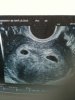

coucou les filles une petite photo de mon écho

Pièces jointes

• IMG_0137.jpg